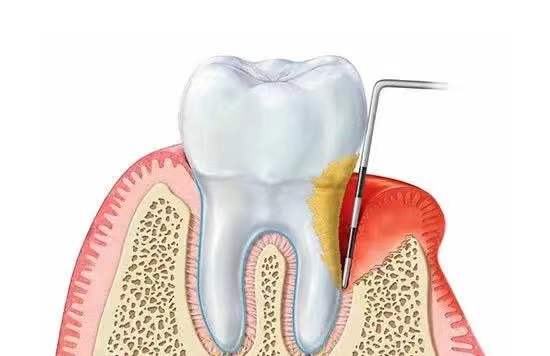

此外牙龈发炎也会让牙根周围的骨质吸收加剧,减少种植体的使用年限,容易出现种完牙没多久就发生晃动、松脱的现象。

是否需要植骨取决于牙槽骨的条件,缺牙多年或本身有严重的牙周病等情况容易导致牙槽骨萎缩。牙槽骨吸收使牙齿根基变浅,牙齿变长,随着骨吸收现象的日趋加剧,牙齿自然也就脱落得更多了。

很多老年人缺牙不补,久而久之引发牙周炎症,一旦发展到重度,会造成牙龈萎缩和牙槽骨损伤;或者因为骨质疏松而骨量不足。